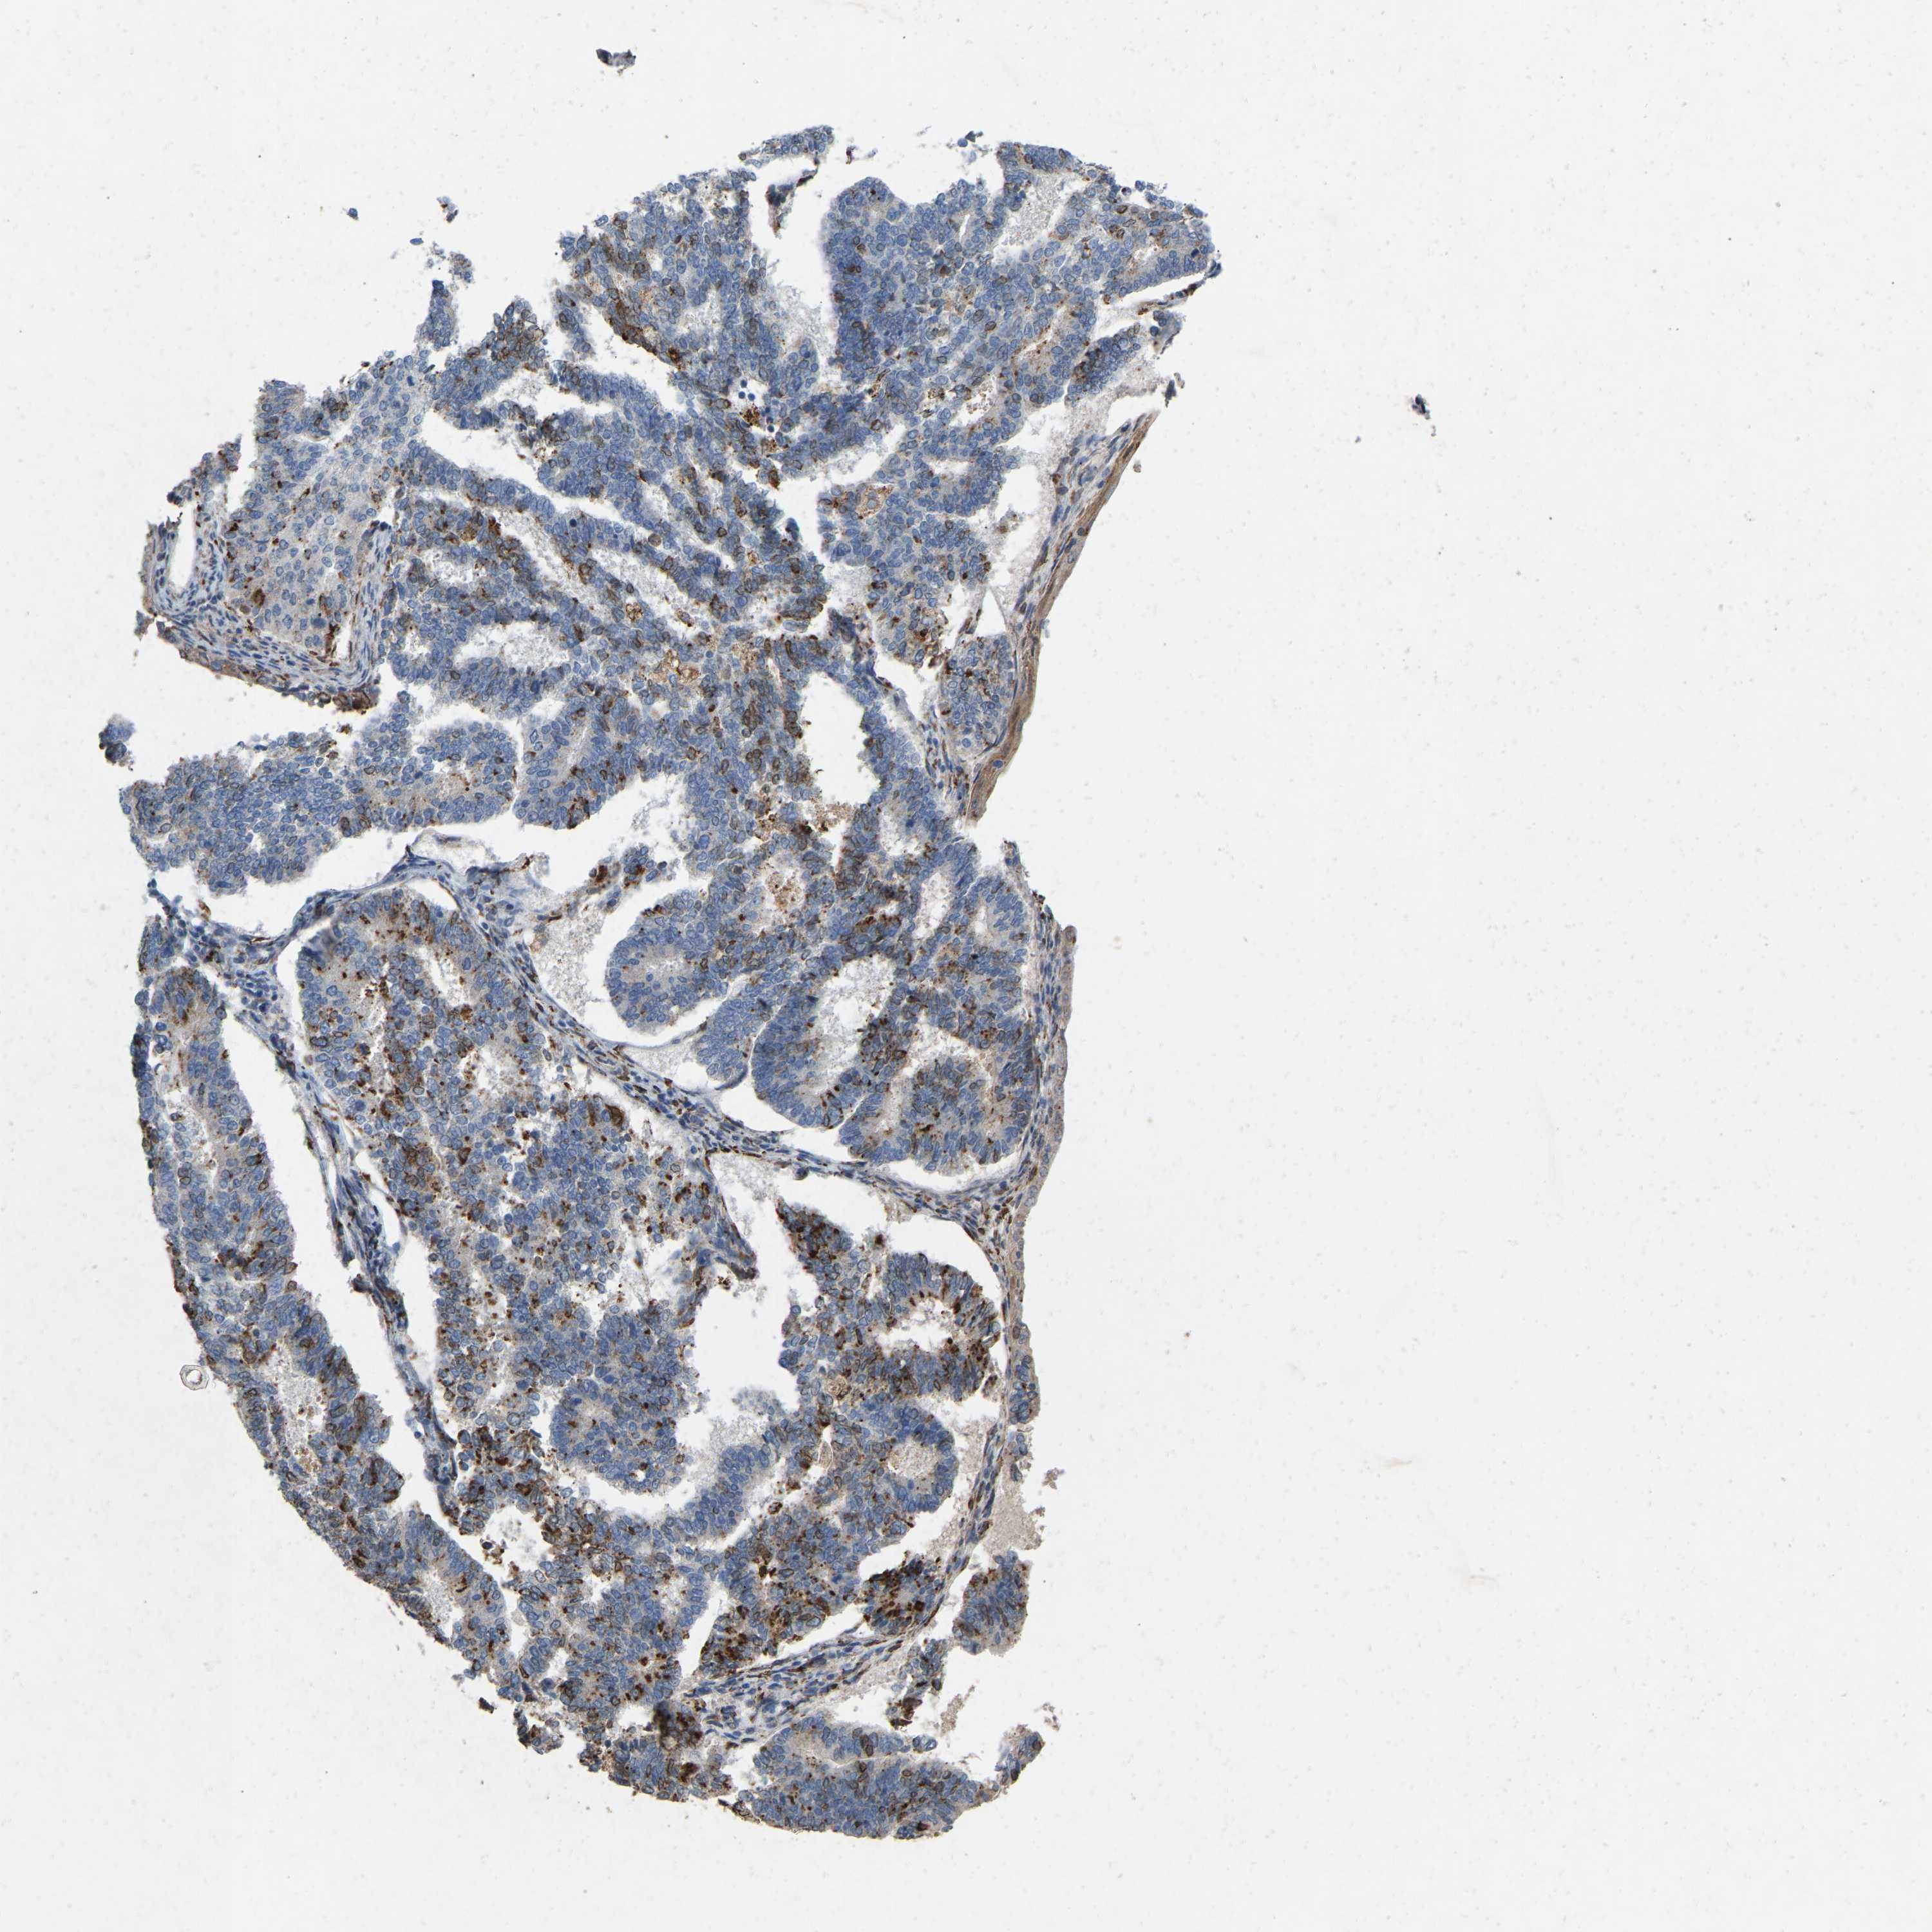

ENDOMETRIAL CANCER - Protein expressioni

A mouse-over function shows sample information and annotation data. Click on an image to view it in a full screen mode. Samples can be filtered based on level of antibody staining by selecting one or several of the following categories: high, medium, low and not detected. The assay and annotation is described here.

Note that samples used for immunohistochemistry by the Human Protein Atlas do not correspond to samples in the TCGA dataset.

Antibody stainingi

Antibody staining in the annotated cell types in the current human tissue is reported as not detected, low, medium, or high, based on conventional immunohistochemistry profiling in selected tissues. This score is based on the combination of the staining intensity and fraction of stained cells.

Each image is clickable and will lead to virtual microscopy that enables deeper exploration of all samples and also displays staining intensity scores, fraction scores and subcellular localization as well as patient and tissue information for each sample.

Antibody CAB019436

Staining

High

Medium

Low

Not detected

Intensity

Strong

Moderate

Weak

Negative

Quantity

>75%

75%-25%

<25%

None

Location

Nuclear

Cytoplasmic/membranous

Cytoplasmic/membranous,nuclear

Adenocarcinoma, NOS